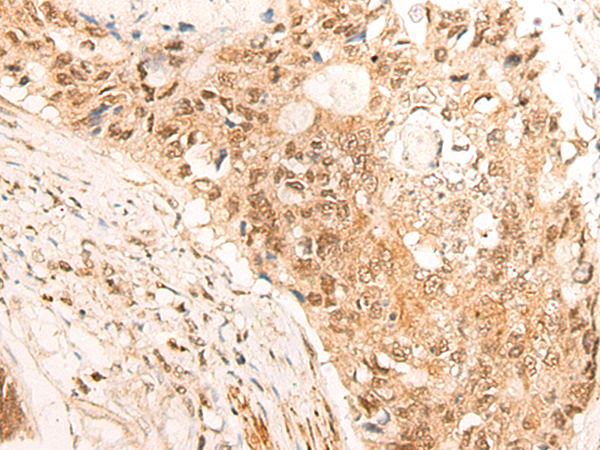

IHC positive control: |

Human tonsil and Human colorectal cancer |